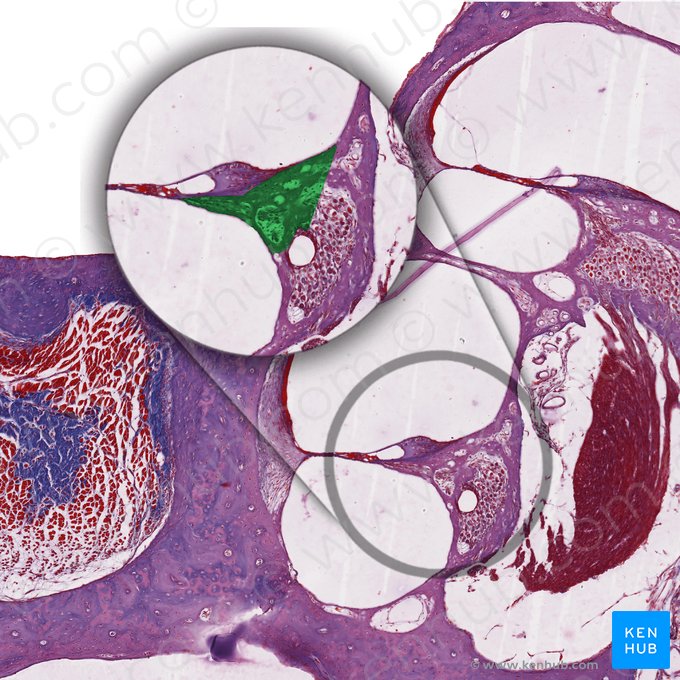

Die Cochlea, die sich im Innenohr befindet, weist eine besondere Mikroanatomie auf. Sie beherbergt das Corti-Organ, das eigentliche Hörorgan, welches aus Sinneszellen, Stützzellen und Nervenfasern besteht. Das Vestibularorgan ist ebenfalls ein Teil des Innenohrs. Es besteht aus drei Bogengängen und zwei Makulaorganen und stellt das Gleichgewichtsorgan dar.